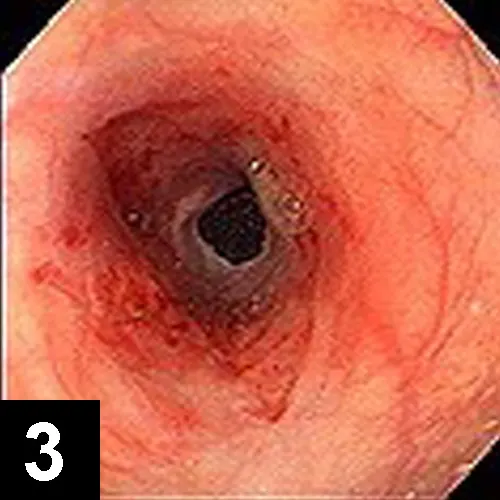

The most likely cause of this abnormality is an intramural esophageal stricture. Unlikely causes for esophageal narrowing include extrinsic extraesophageal compression from neoplasia or inflammation, vascular ring anomaly, presence of an esophageal foreign body, or esophageal neoplasia. Endoscopy was done to delineate the obstruction and to perform therapeutic esophageal dilatation. Figure 2 shows the esophageal narrowing at the thoracic inlet. Figure 3 shows the esophagus following a balloon dilatation procedure.

Figure 3. The esophageal stricture after dilatation to 16 mm diameter

Treatment Plan. Feed a liquid diet or attempt to dilate the stricture. Surgical resection is considered to be less successful. Several dilatation instruments have been described, but dilatation with a balloon seems to be the safest and most successful method. Balloons of increasing diameter are inserted into the lumen and then inflated under pressure to open the lumen to the desired diameter. In this case, the stricture was dilated to 16 mm in diameter over a course of three sessions at weekly intervals. Some authors recommend systemic or intralesional injections of steroids to reduce inflammation and stricture contraction. This cat was also treated with intralesional injections of triamcinolone in the stricture site using an endoscopic injection needle. It made an uneventful recovery and now consumes canned food without problems.